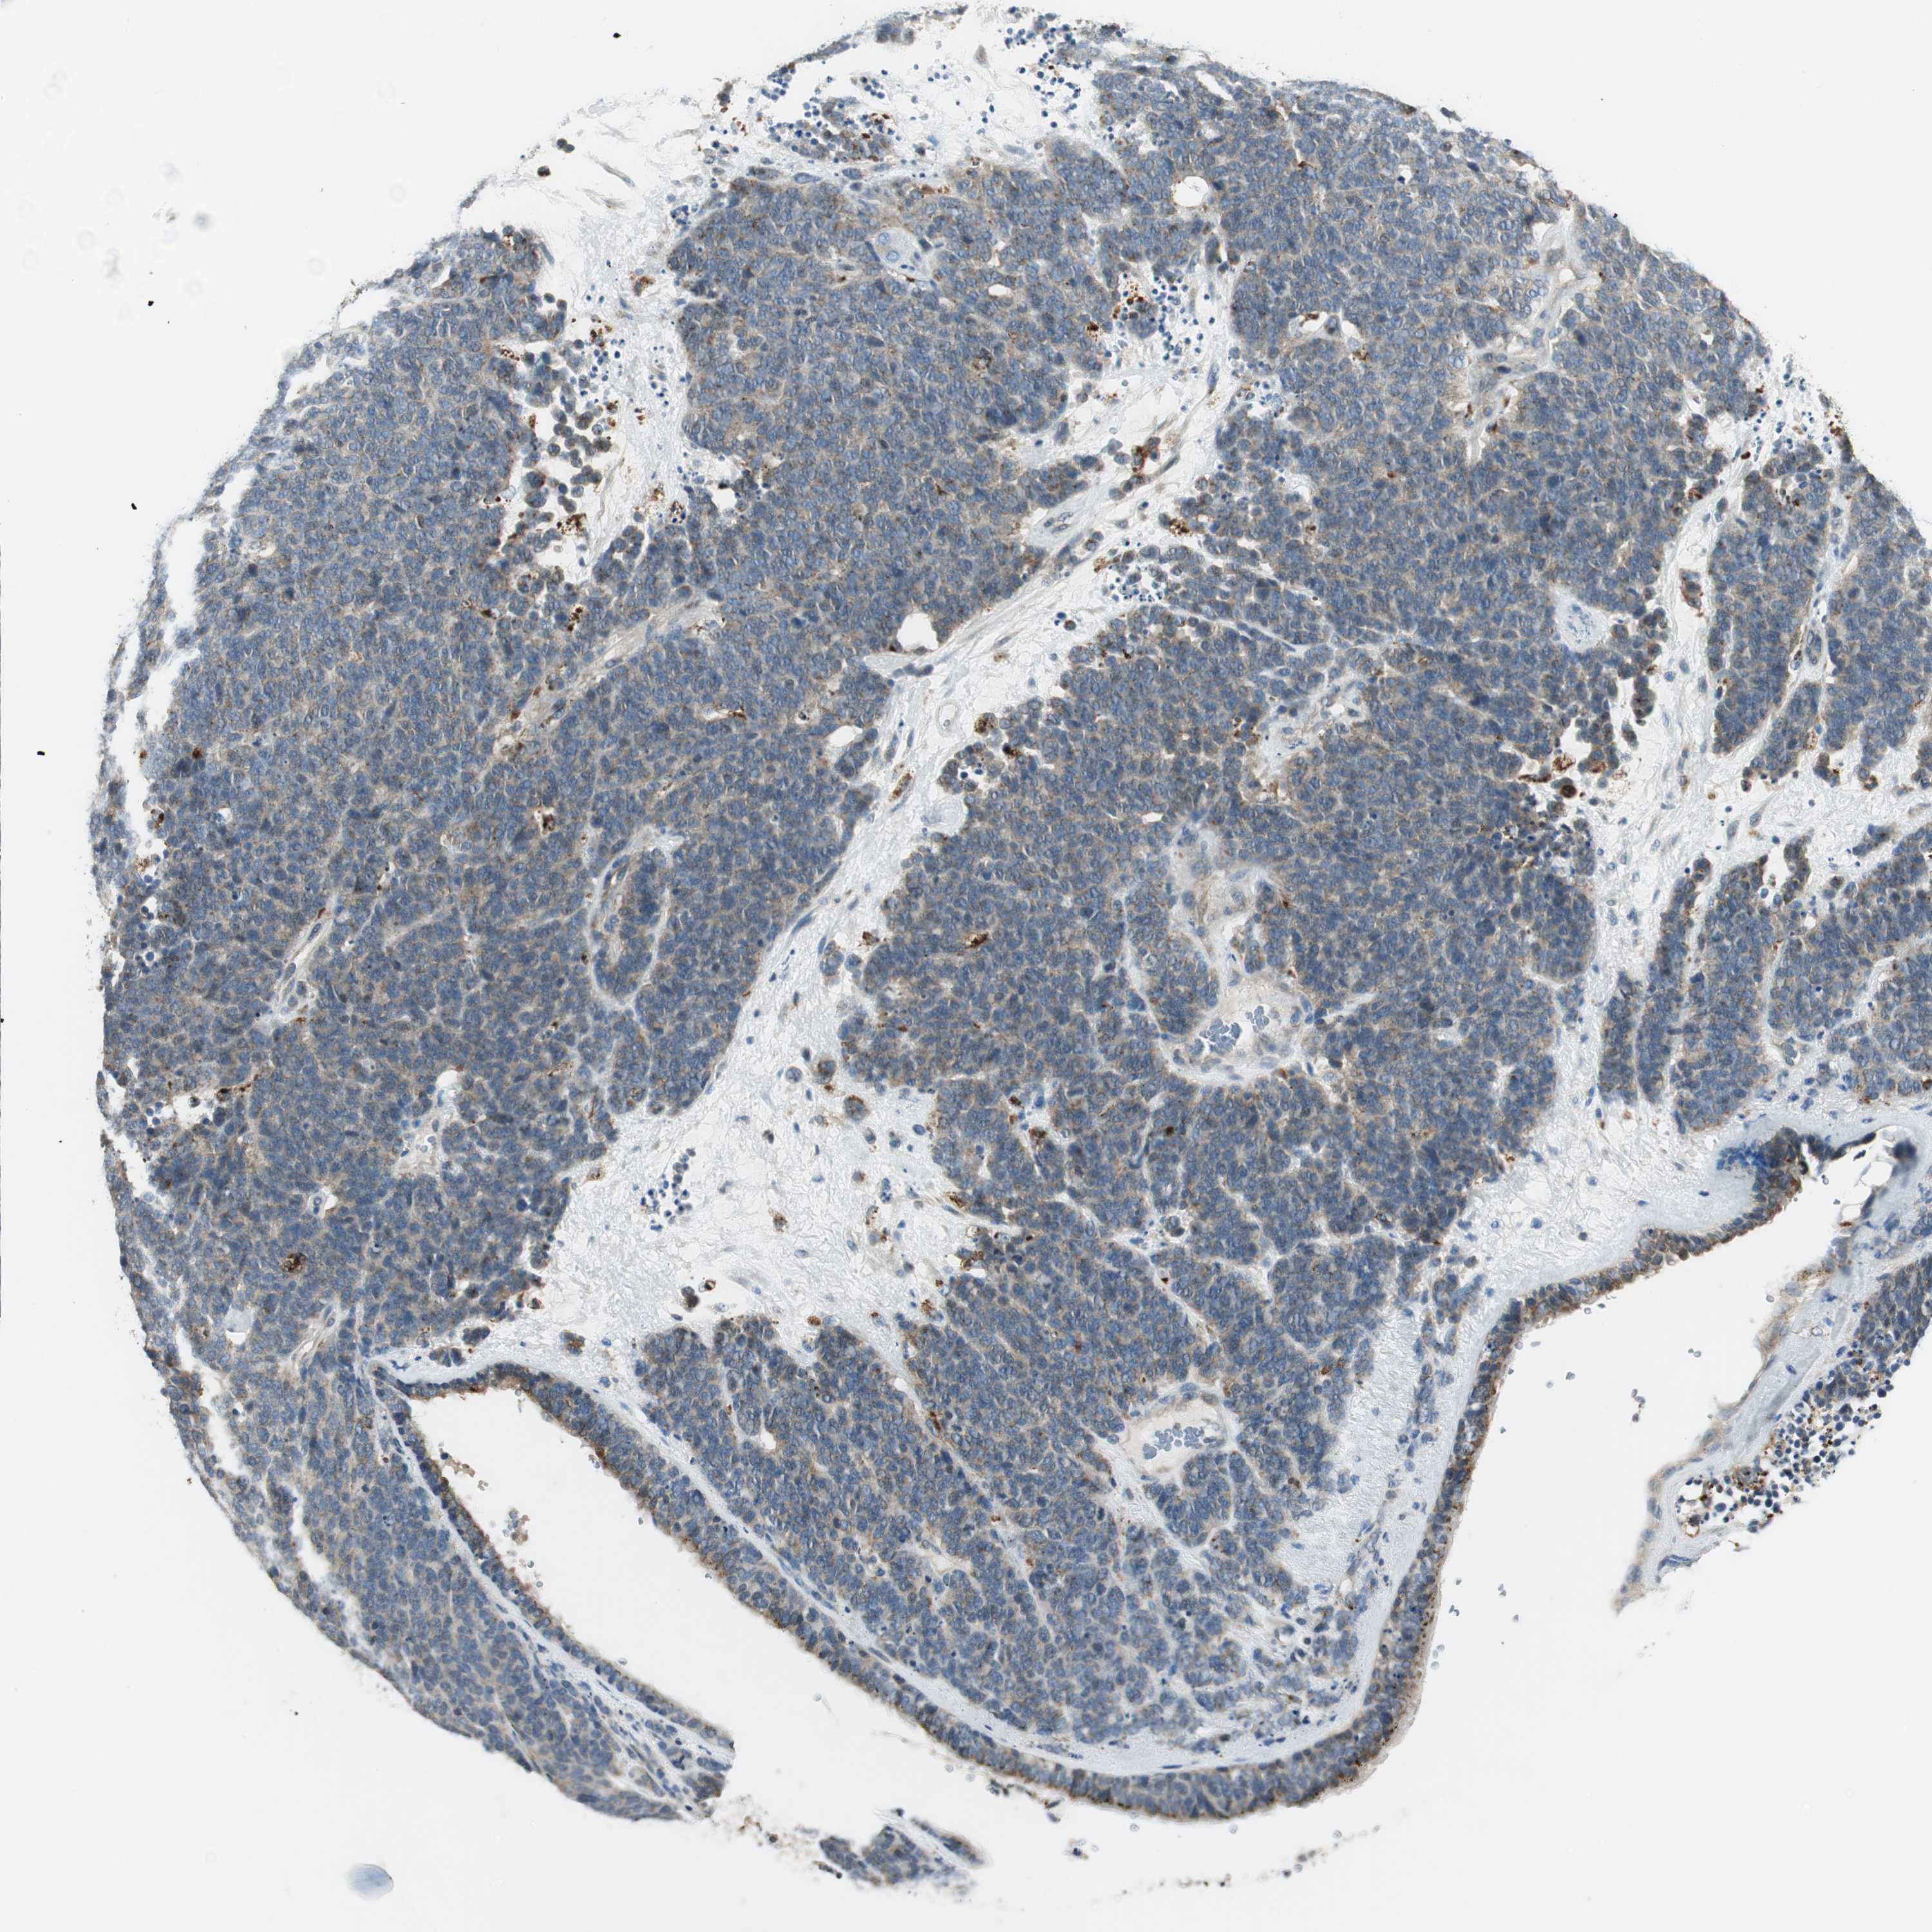

LUNG SQUAMOUS CELL CARCINOMA (TCGA) - Interactive survival scatter ploti

The Survival Scatter plot shows the clinical status (i.e. dead or alive) for all individuals in the patient cohort, based on the same data that underlies the corresponding Kaplan-Meier plots. Patients that are alive at last time for follow-up are shown in blue and patients who have died during the study are shown in red.

The x-axis shows the expression levels (FPKM) of the investigated gene in the tumor tissue at the time of diagnosis. The y-axis shows the follow-up time after diagnosis (years). Both axes are complimented with kernel density curves demonstrating the data density over the axes. The top density plot shows the expression levels (FPKM) distribution among dead (red) and alive patients (blue). The right density plot shows the data density of the survived years of dead patients with high and low expression levels respectively, stratified using the cutoff indicated by the vertical dashed line through the Survival Scatter plot. This cutoff is automatically defined based on the FPKM cutoff that minimizes the p-score. The cutoff can be changed by dragging the vertical line or by entering a cutoff value in the square labeled "Current cut-off".

Under the Survival Scatter plot the p-score landscape (black curve; left axis) is shown together with dead median separation (red curve; right axis). Dead median separation is the difference in median mRNA expression between patients who have died with high and low expression, respectively. It is calculated as follows: median FPKM expression of dead patients with high expression - median FPKM expression of dead patients with low expression. This is intended to aid the user in visually exploring custom cutoffs and the associated p-scores and dead median separation.

Individual patient data is displayed and can be filtered by clicking on one or more of the category buttons on the top of the page. Categories describing expression level and patient information include: high, low, alive, dead, female, male and tumor stages. The scale of the x-axis can be toggled between linear and log-scale by clicking on the "x log" button. Mouse-over function shows TCGA ID, patient information and mRNA expression (FPKM) for each patient.

& Survival analysisi

Kaplan-Meier plots summarize results from analysis of correlation between mRNA expression level and patient survival. Patients were divided based on level of expression into one of the two groups "low" (under cut off) or "high" (over cut off). X-axis shows time for survival (years) and y-axis shows the probability of survival, where 1.0 corresponds to 100 percent.

NCK1 is not prognostic in Lung Squamous Cell Carcinoma (TCGA)

: 59.3